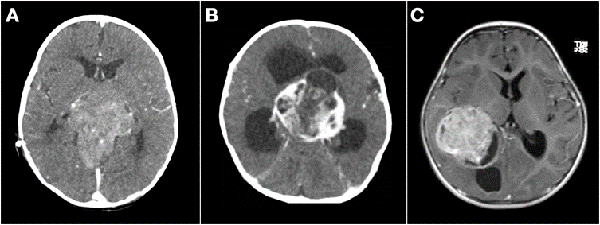

Se realizó biopsia en 3 lesiones de tronco cerebral, 1 lesión pineal abordada endoscópicamente, 1 lesión hipotalámico-quiasmática, 1 lesión frontal subcortical y 1 lesión centroencefálica extensa. En los dos últimos casos se efectuó sólo biopsia por el intenso sangrado que obligó a suspender el procedimiento. El diagnóstico histológico fue tumor embrionario en ambos, por lo que se trataron con quimioterapia (Figura 5-B).

Un tema controvertido es definir cuando un tumor de SNC es congénito. Solitare et al. 14 los divide en: "definitivamente congénitos" que son aquellos que producen síntomas al nacer, "cercanamente congénitos" que son los que producen síntomas dentro de la primera semana de vida, y "probablemente congénito" que son los que se manifiestan dentro del primer mes de vida. La inclusión de pacientes de hasta 2 meses de edad fue propuesta por Arnstein et al. 1 siendo este el límite más aceptado para definir el origen congénito. Sin embargo, hay otros autores como Jellinger y Manoranjan16,17 que extienden esta definición al primer año de vida. Con base en las definiciones de los últimos dos investigadores, nuestra serie presentó 26 casos menores de un año, de los cuales solo 3 fueron menores de 2 meses de vida, todos ellos tumores embrionarios (2 indiferenciados y 1 teratoma inmaduro) (Figuras 2 y 5 B).

Figura 5: Tumores agresivos. A) Paciente de 8 meses de vida, sexo masculino, presentó irritabilidad, macrocefalia y somnolencia. TC de cerebro con contraste EV donde se observó imagen en región pineal que se extiende al tercer ventrículo. Se realizó cirugía de exploración, exéresis parcial, anatomía patológica informó pineoblastoma, paciente falleció a los 5 meses por progresión de la enfermedad. B) Paciente de 2 meses de vida, sexo masculino, consultó por deterioro progresivo del sensorio. TC de cerebro con contraste EV que evidenció lesión centroencefálica e hidrocefalia obstructiva. Se realizó cirugía de exploración de lesión, con colocación intraquirúrgica de drenaje ventricular al exterior. Anatomía patológica informó tumor embrionario indiferenciado. Paciente falleció a los 14 días por progresión de enfermedad. C) Paciente de 19 meses de vida, sexo femenino, consultó por vómitos a repetición. IRM de cerebro con contraste EV que mostró tumor supratentorial intraventricular con realce homogéneo con el contraste EV. Se realizó cirugía de exploración, con exéresis parcial por el intenso sangrado. Anatomía patológica informó carcinoma de plexos coroideos. Paciente fallece a los 3 meses.

Analizando por separado los resultados de anatomías patológicas vemos que los ATRT, meduloblastomas y ependimomas tuvieron una supervivencia del 32% a los 5 años (Figuras 3 y 4) y los pacientes con tumores embrionarios, PNET, carcinomas y papilomas atípicos de plexos coroideos y pineoblastomas presentaron una mortalidad del 100% a los 5 años (Figuras 5 y 6). Por otro lado, los papilomas de plexos coroideos, lesiones más frecuentes en el grupo 1, tuvieron un 100% de supervivencia a los 10 años, al igual que los astrocitomas y gliomas de bajo grado (Figuras 7 y 8).